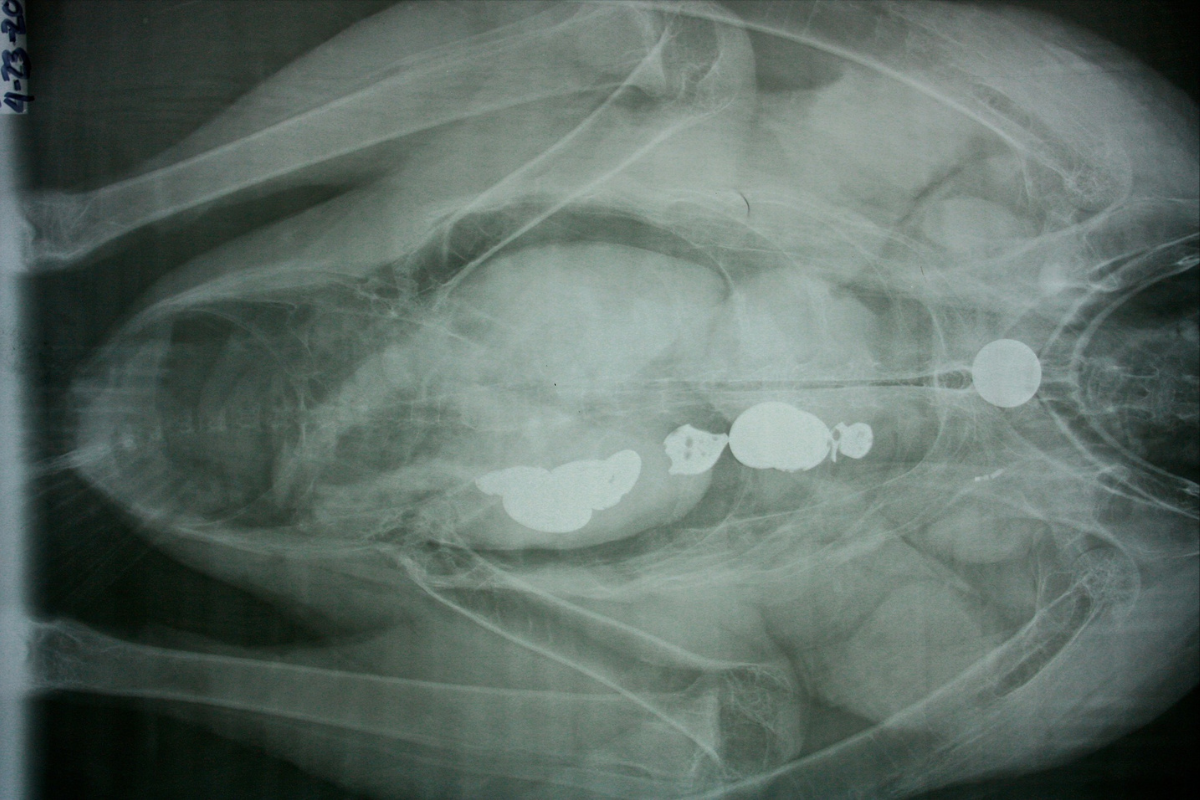

condor x-ray

An X-ray of a condor with coins stuck inside its digestive tract. (Source: NPS)

This habit is a problem for the bird, and an X-ray shared by the National Park Service shows an example of several coins lodged in a condor’s digestive tract. Fortunately, wildlife officials could operate on this bird, but other animals aren’t always so lucky.